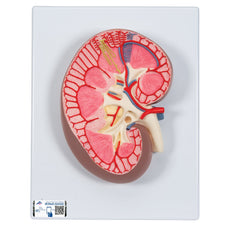

One front half of a kidney is removable from the anatomical model of the urinary system. With easy to change male insert (bladder and prostate, front and rear half) and female insert (bladder, womb and ovaries, 2 lateral halves) the Urinary System model is a great teaching tool.

To get started, simply scan the QR-code located on your 3B Scientific® Anatomical Model, download the new 3B Smart Anatomy app and step into the virtual world of Human Anatomy.